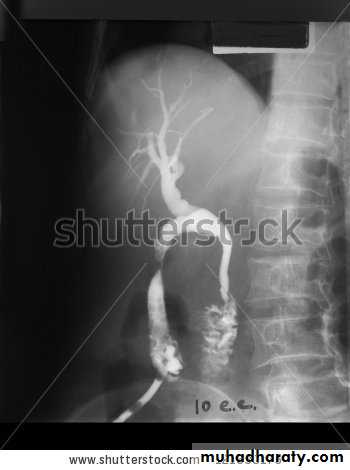

Percutaneous transhepatic cholangiography (PTC)

Under a local anaesthetic, a fine flexible needle is passed into the liver. Contrast is injected slowly until a biliary radicle is identified. Now this test rarly used due to high risks of bleeding, cholangitis and septicemia.